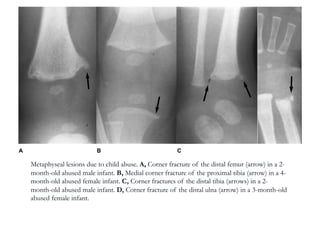

Classic Metaphyseal

Injury

Corner Fracture

Metaphyseal lesions due to child abuse. A, Corner fracture of the distal femur (arrow) in a 2-

month-old abused male infant. B, Medial corner fracture of the proximal tibia (arrow) in a 4-

month-old abused female infant. C, Corner fractures of the distal tibia (arrows) in a 2-

month-old abused male infant. D, Corner fracture of the distal ulna (arrow) in a 3-month-old

abused female infant.